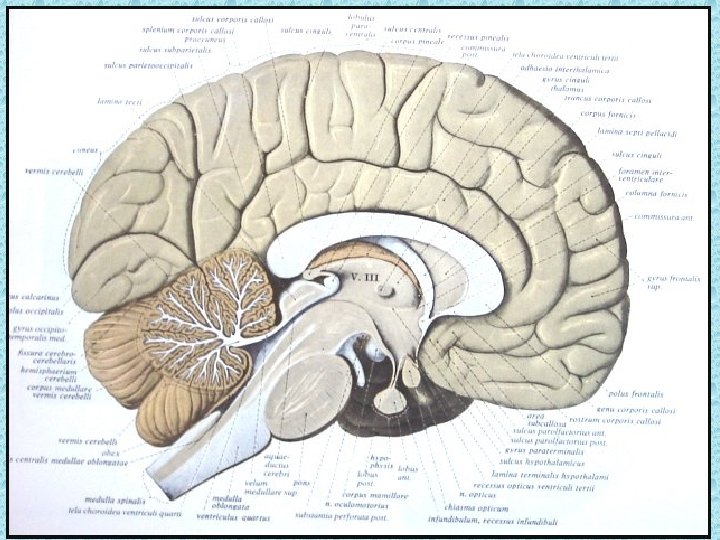

SEREBRAL LOBLAR • • Frontal Paryetal Oksipital Temporal

SEREBRAL PARANKİMDE BULUNAN YAPILAR • • Beyaz ve gri cevher Girus ve sulkuslar Lentiform nükleus: Putamen ve globus pallidus İnternal ve eksternal kapsül Talamus Kaudat nükleus ve korpus kallozum Ventriküller Koroid pleksus

BEYİN SAPI • Medulla oblangata (Bulbus) • Putamen • Mezensefalon

POSTERİOR FOSSADA BULUNAN YAPILAR • • • Serebellum Beyin sapı 4. ventrikül Vermis Transvers ve sigmoid sinüs

BEYİN ZARLARI • Dura mater • Araknoid mater • Pia mater

VENTRİKÜLLER • Lateral ventriküller: frontal, oksipital ve temporal hornlar, korpus ve atrium • Foramen monro • 3. Ventrikül • Akuaduktus silvii • 4. Ventrikül • Foramen Lucka (çift) ve magendi (tek)